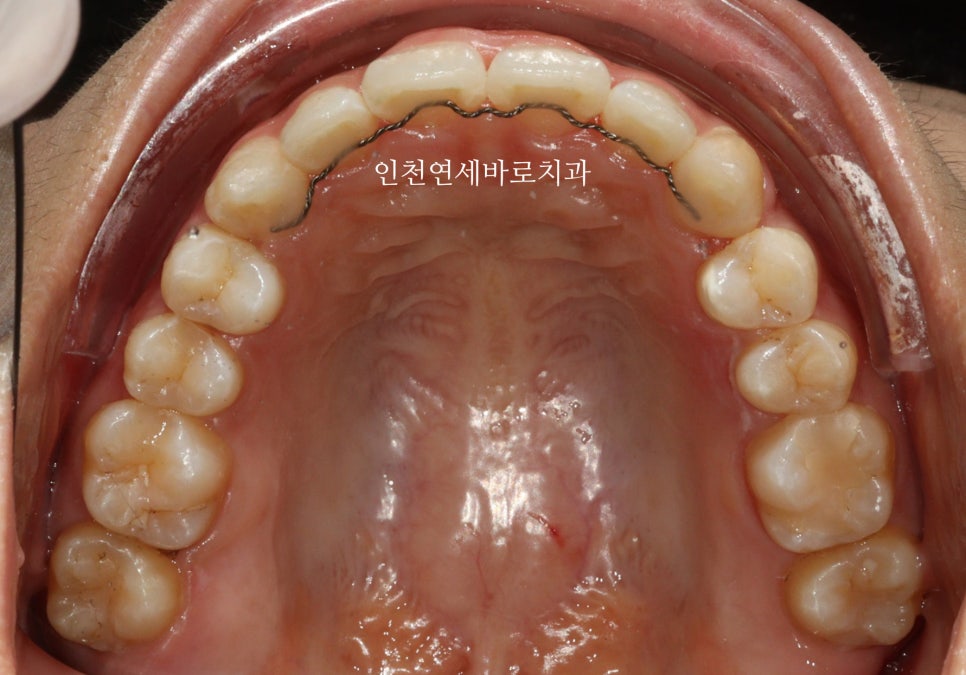

이 환자분은 14개의 장치가 끝난 후 한번의 재제작을 했습니다

위 사진이 7월에 재제작 했을 때 모습입니다.

2월초부터 장치를 착용했고 10월에 마무리 했습니다.

1개의 장치를 7일씩 착용하고, 중간에 재제작 한달이라는 기간이 포함된 기간입니다.

전후 비교입니다

전 후 교합의 비교입니다.

안정적으로 교합이 형성되었습니다